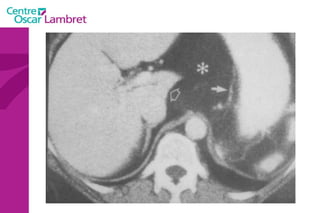

Adénopathies Rétro-crurale inter-aortico-cave

Adénopathies Rétro-cave mésentériques vci